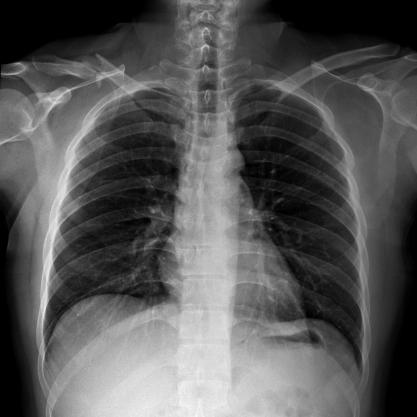

滿(mǎn)足不同身高的受檢者快速地進(jìn)行胸片的靜態(tài)及動(dòng)態(tài)檢查,適合大規(guī)模體檢。

SID可拉伸至1.8米,滿(mǎn)足標(biāo)準(zhǔn)胸片、職業(yè)性塵肺病檢查等特殊需求。